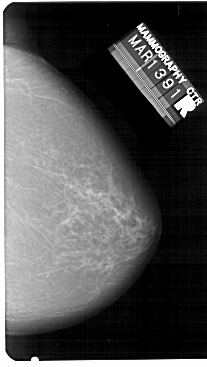

A_1341_1.RIGHT_MLO

RIGHT_MLO LINES 5491 PIXELS_PER_LINE 3496 BITS_PER_PIXEL 12 RESOLUTION 43.5 NON_OVERLAY